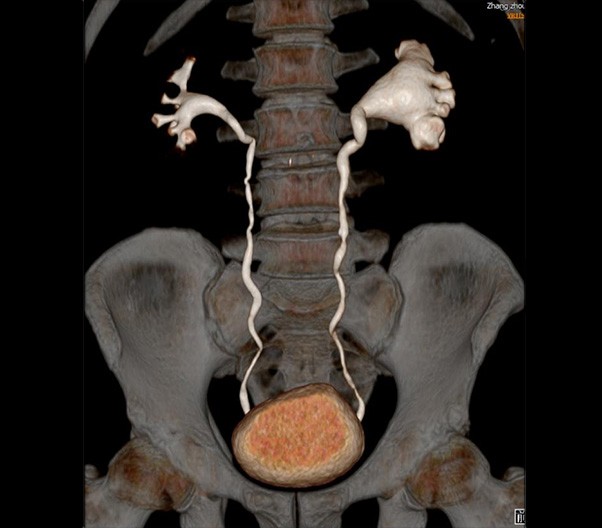

The 1024-pixel image matrix brings superior image clarity (0.6 mm slice thickness) and stimulates the early detection of small lesions, thus improving diagnostic reliance.

ScintCare CT 16 incorporates an entirely digital integrated ScintiStar detector, which was solely developed by MinFound, from material to the whole structure design, based on the technical know-how of our skilled scientific team. The system produces high-resolution images with a low radiation dose and an excellent signal-to-noise ratio.

臨床畫廊